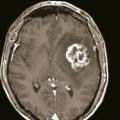

• un abcès cérébral (fig. 4) en présence d’un syndrome fébrile, d’un foyer infectieux, en particulier quand la prise de contraste est annulaire, un tuberculome en cas de contage ou terrain à risque ;